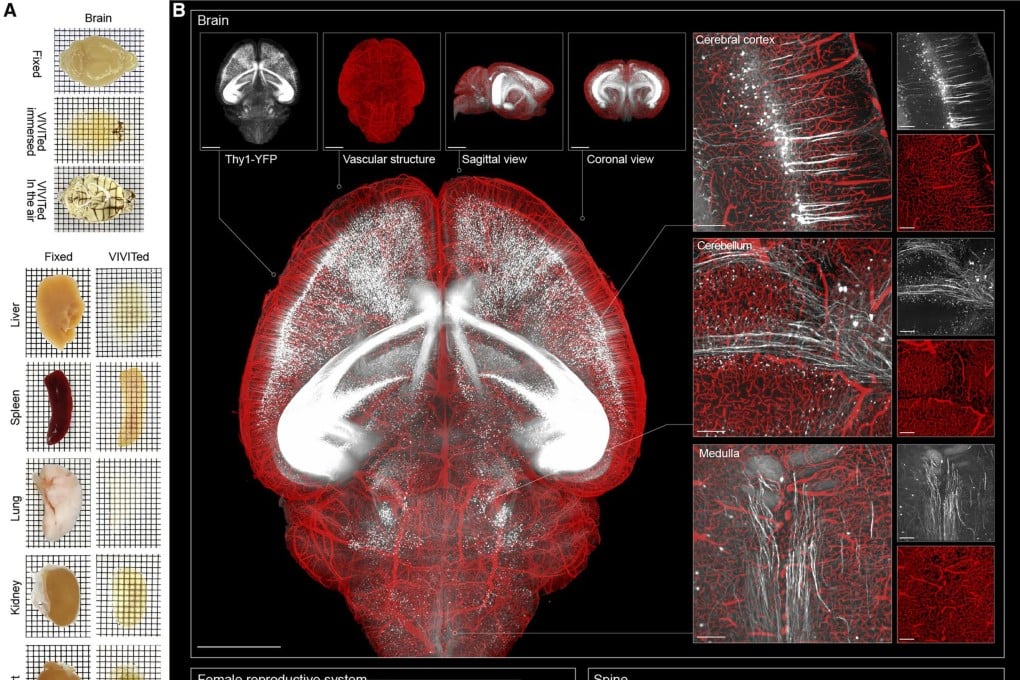

دانشمندان چینی موفق به توسعه تکنیک جدیدی شدهاند که باعث شفافسازی اندامها شده و در عین حال، ساختار آنها را حفظ میکند. این تکنیک میتواند در آینده برای ایجاد تصاویر بسیار دقیق و واضح مورد استفاده قرار بگیرد. در این بخش خبری از گجت نیوز با ما همراه باشید.

تکنیک جدید کشف شده از سوی دانشمندان چینی ممکن است کمک بسیار خوبی برای مشاهده درون کل اندامها بدون نیاز به تشریح آنها باشد.

این مایع توانایی ورود به اندام را داشته و آنها را به چیزی تبدیل میکند که حالت شیشهای یونی نامیده میشود. در این حالت بافت شفاف شده و شکل اصلی یا ساختار ظریف خود را حفظ میکند، چرا که خبری از منبسط یا منقبض شدن نیست.

مایعهای یونی هنگام خنک شدن، کریستال تشکیل نخواهند داد و این اجازه را میدهد بافتهای درمان شده برای مدت طولانی در انبار سرد هم نگهداری شود. این فرایند رنگهای فلورسنت را به میزان زیادی افزایش داده و موجب میشود ۲ تا ۳۰ برابر روشنتر باشند.

هم اکنون به لطف تکنیک جدید کشف شده، سیگنالهای ضعیف مانند پروتئینهای نادر یا اتصالهای ظریف نورونی هم قابل مشاهده هستند.

این تکنیک میتواند پیامدهای عظیم برای کاربردهایی مانند تصویربرداری سهبعدی داشته باشد و محققان را قادر خواهد ساخت با دقت بیشتری از کل اندامها در مقیاس میکروسکوپی نقشهبرداری کنند.

در تئوری میتوان گفت تکنیک موردنظر در طیف وسیعی از اندامها مانند مغز، طحال و هر چیزی در میان آنها استفاده میشود.